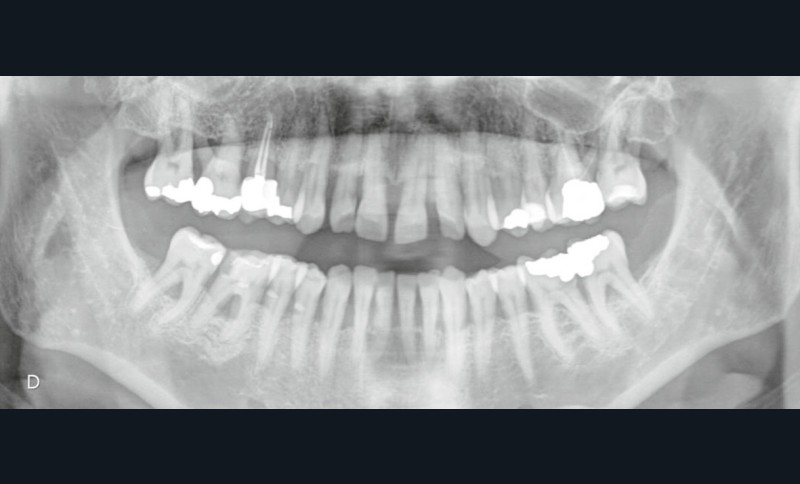

L’examen radiographique (fig. 3-5) nous indique une Classe I squelettique de Ballard (ANB 0°) sur un schéma facial à tendance hyperdivergent (FMA 28°). L’analyse céphalométrique confirme la vestibulo-version incisive (I/SN 111° ; IMPA 94°). La lyse osseuse est généralisée.